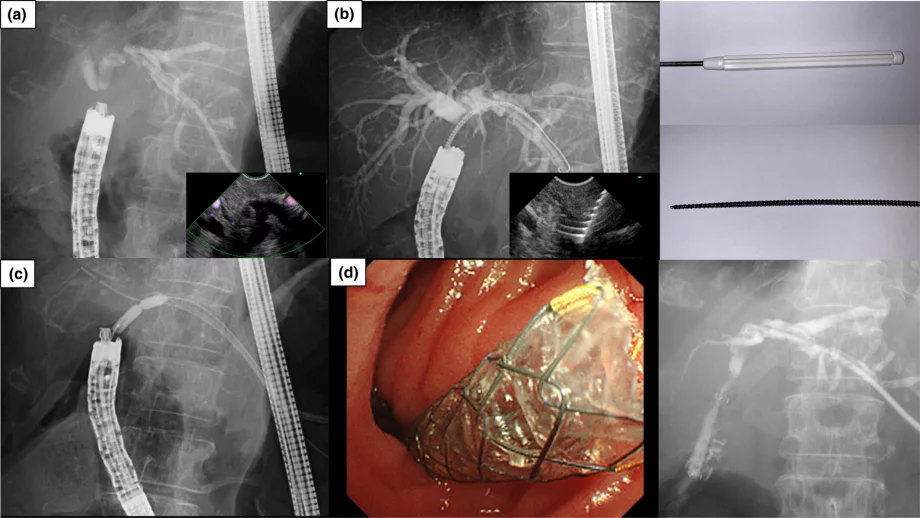

Sliding tube-assisted ERCP in a patient who underwent double tract reconstruction anatomy after proximal gastrectomy

Koichiro Kawano, Mamoru Takenaka, Reiko Kawano, Takao Katoh, Katsuhisa Nishi, Chang-Il Kwon, Masatoshi Kudo